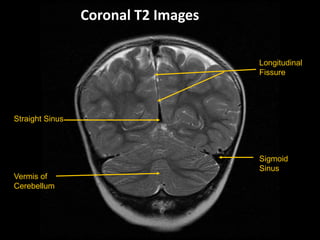

Coronal T2 Images

Longitudinal

Fissure

Sigmoid

Sinus

Straight Sinus

Vermis of

Cerebellum